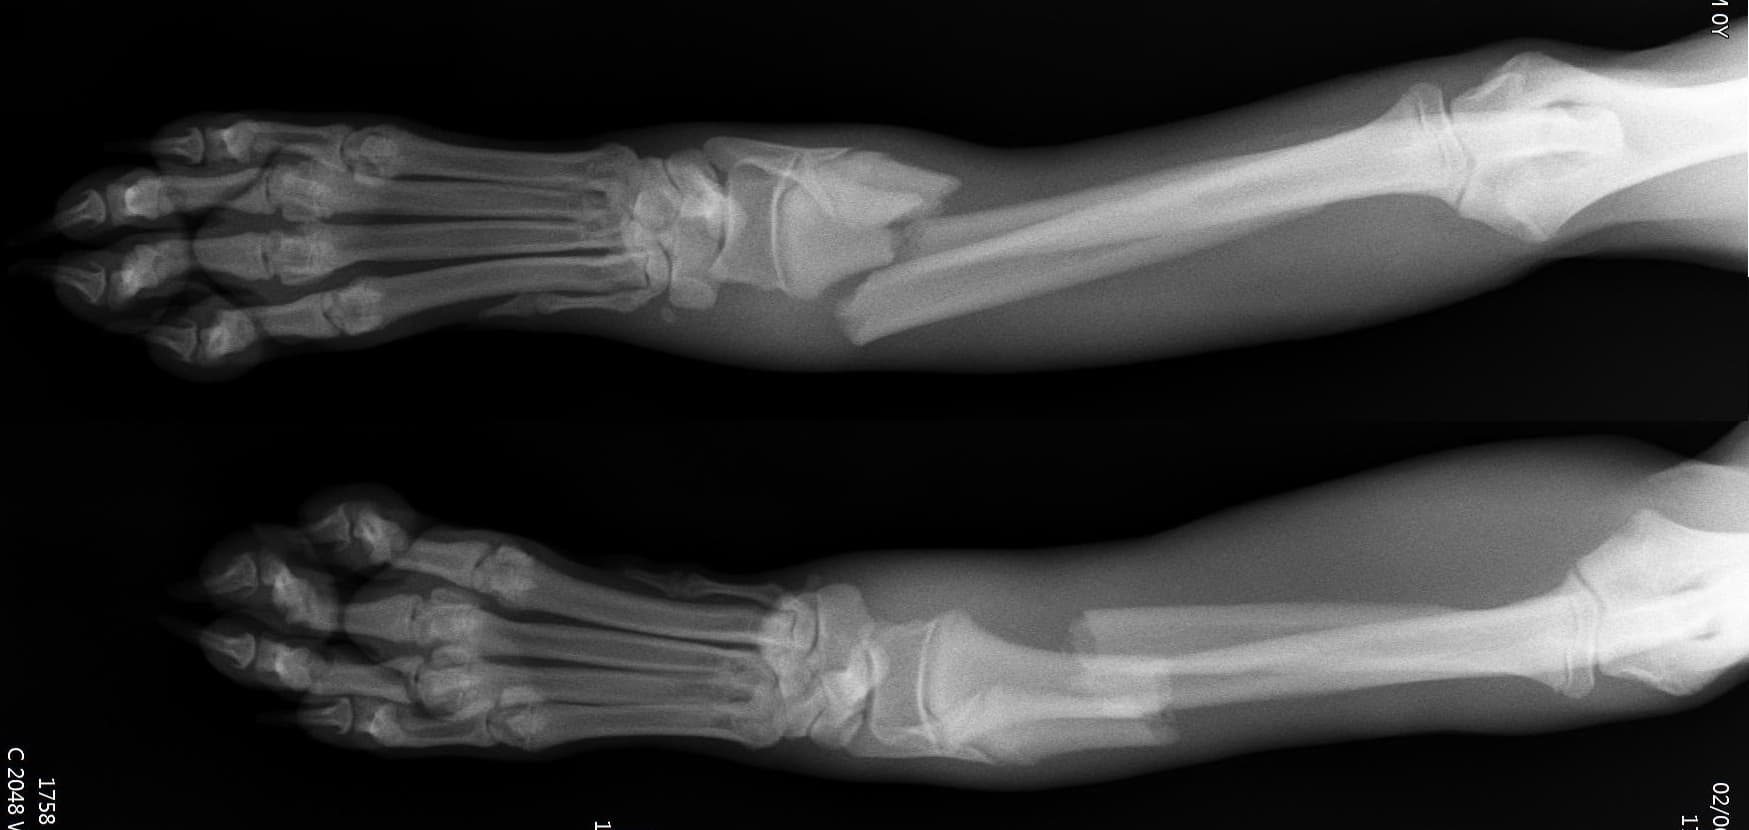

정형외과 전공의 수의사가 직접 수술합니다.

0164 채널 CT 촬영을 통해서 신속하게 고화질 영상을 얻어, 종양 유래 확인 및 전이 평가, 간문맥단락증(PSS), 선천적 뼈 기형과 같은 심화된 진단을 할 수 있습니다.

02C-arm을 통해서 좀 더 섬세한 정형외과 수술을 진행하고, 본원에서는 외과적 침습을 최소화 하는 중재적 시술 (기관 협착, 동맥관개존증(PDA), SUB 등)을 진행하고 있습니다.

12정교한 정형외과 도구를 사용하여 신속 정확한 정형외과 수술이 가능

13수술 중 골절 상태 혹은 이식물 적용 후 상태 등 육안으로 명확히 확인하기 힘든 상태를 X-ray 확인하여 정확한 수술 결과를 만들어 내는 것이 가능